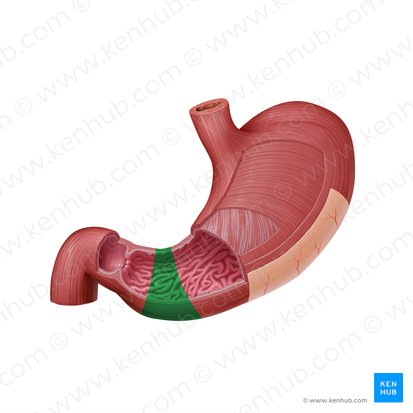

Pyloric sphincter

A muscular ring located at the junction of the stomach and the duodenum (the first part of the small intestine) that controls the emptying of stomach contents into the duodenum.

Pyloric canal

the narrow passageway that leads from the pyloric antrum to the pyloric sphincter.

Pyloric antrum

The funnel-shaped region of the stomach that precedes the pyloric canal.

Pylorus

The distal, narrow region of the stomach that connects to the duodenum, including the pyloric antrum, pyloric canal, and pyloric sphincter.

Duodenum

This is the first and shortest segment of the small intestine. It receives partially digested food (known as chyme).

Receives digestive enzymes from the pancreas and bile from the liver and gallbladder through the pancreatic and bile ducts.